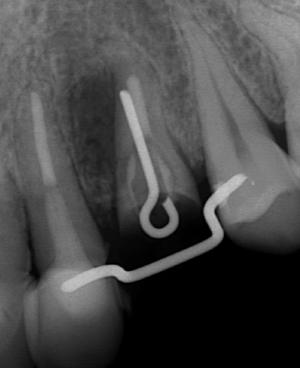

CT撮影 根の脇に大きな病巣を確認。根管治療でのパーフォレーション(穿孔、穴が開く)が原因。